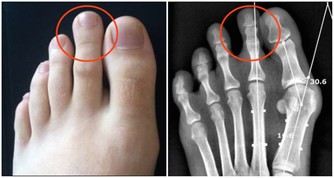

(9)肝掌

“肝掌”可以說是肝臟受損最明顯的信號。

肝掌,是拇指根部和小指根部的片狀充血,面積或大或小,只要稍加壓力之後,充血部位會由紅色變成蒼白色。